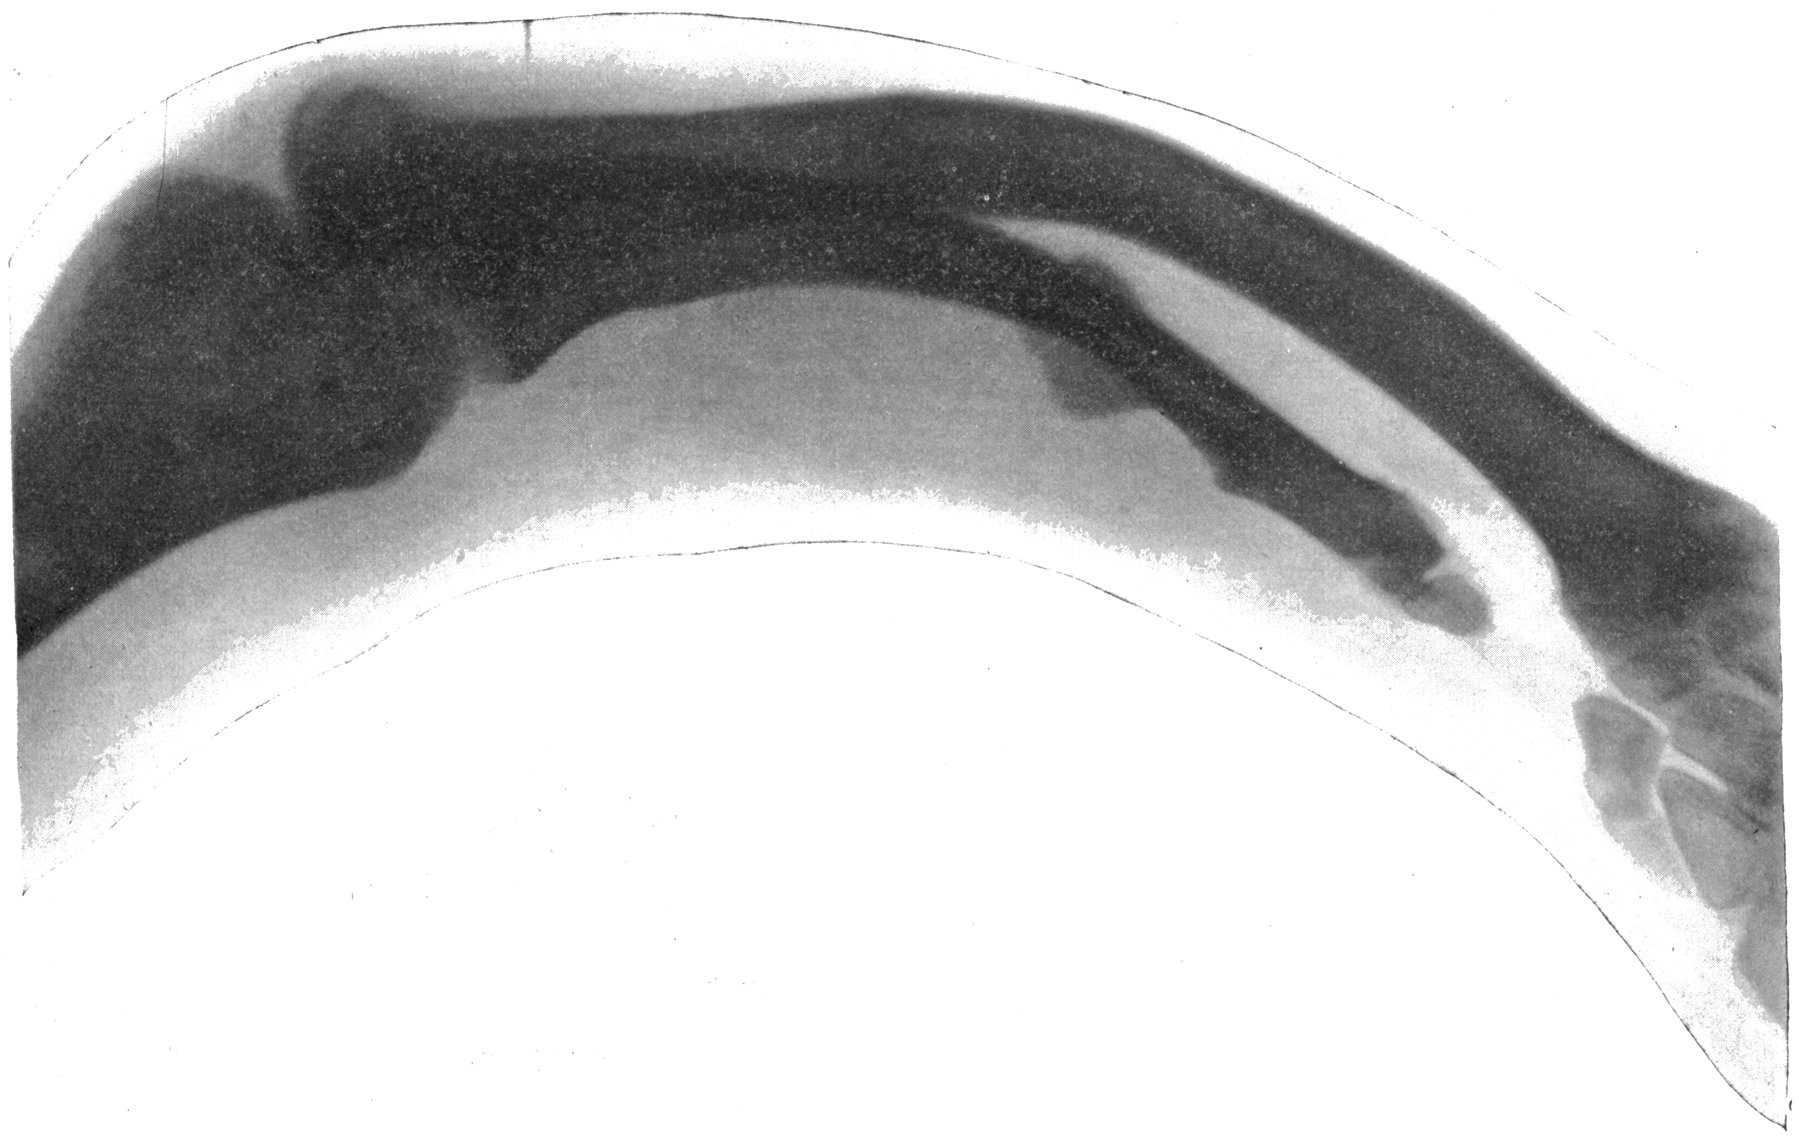

Fig. 3.—Ribs.